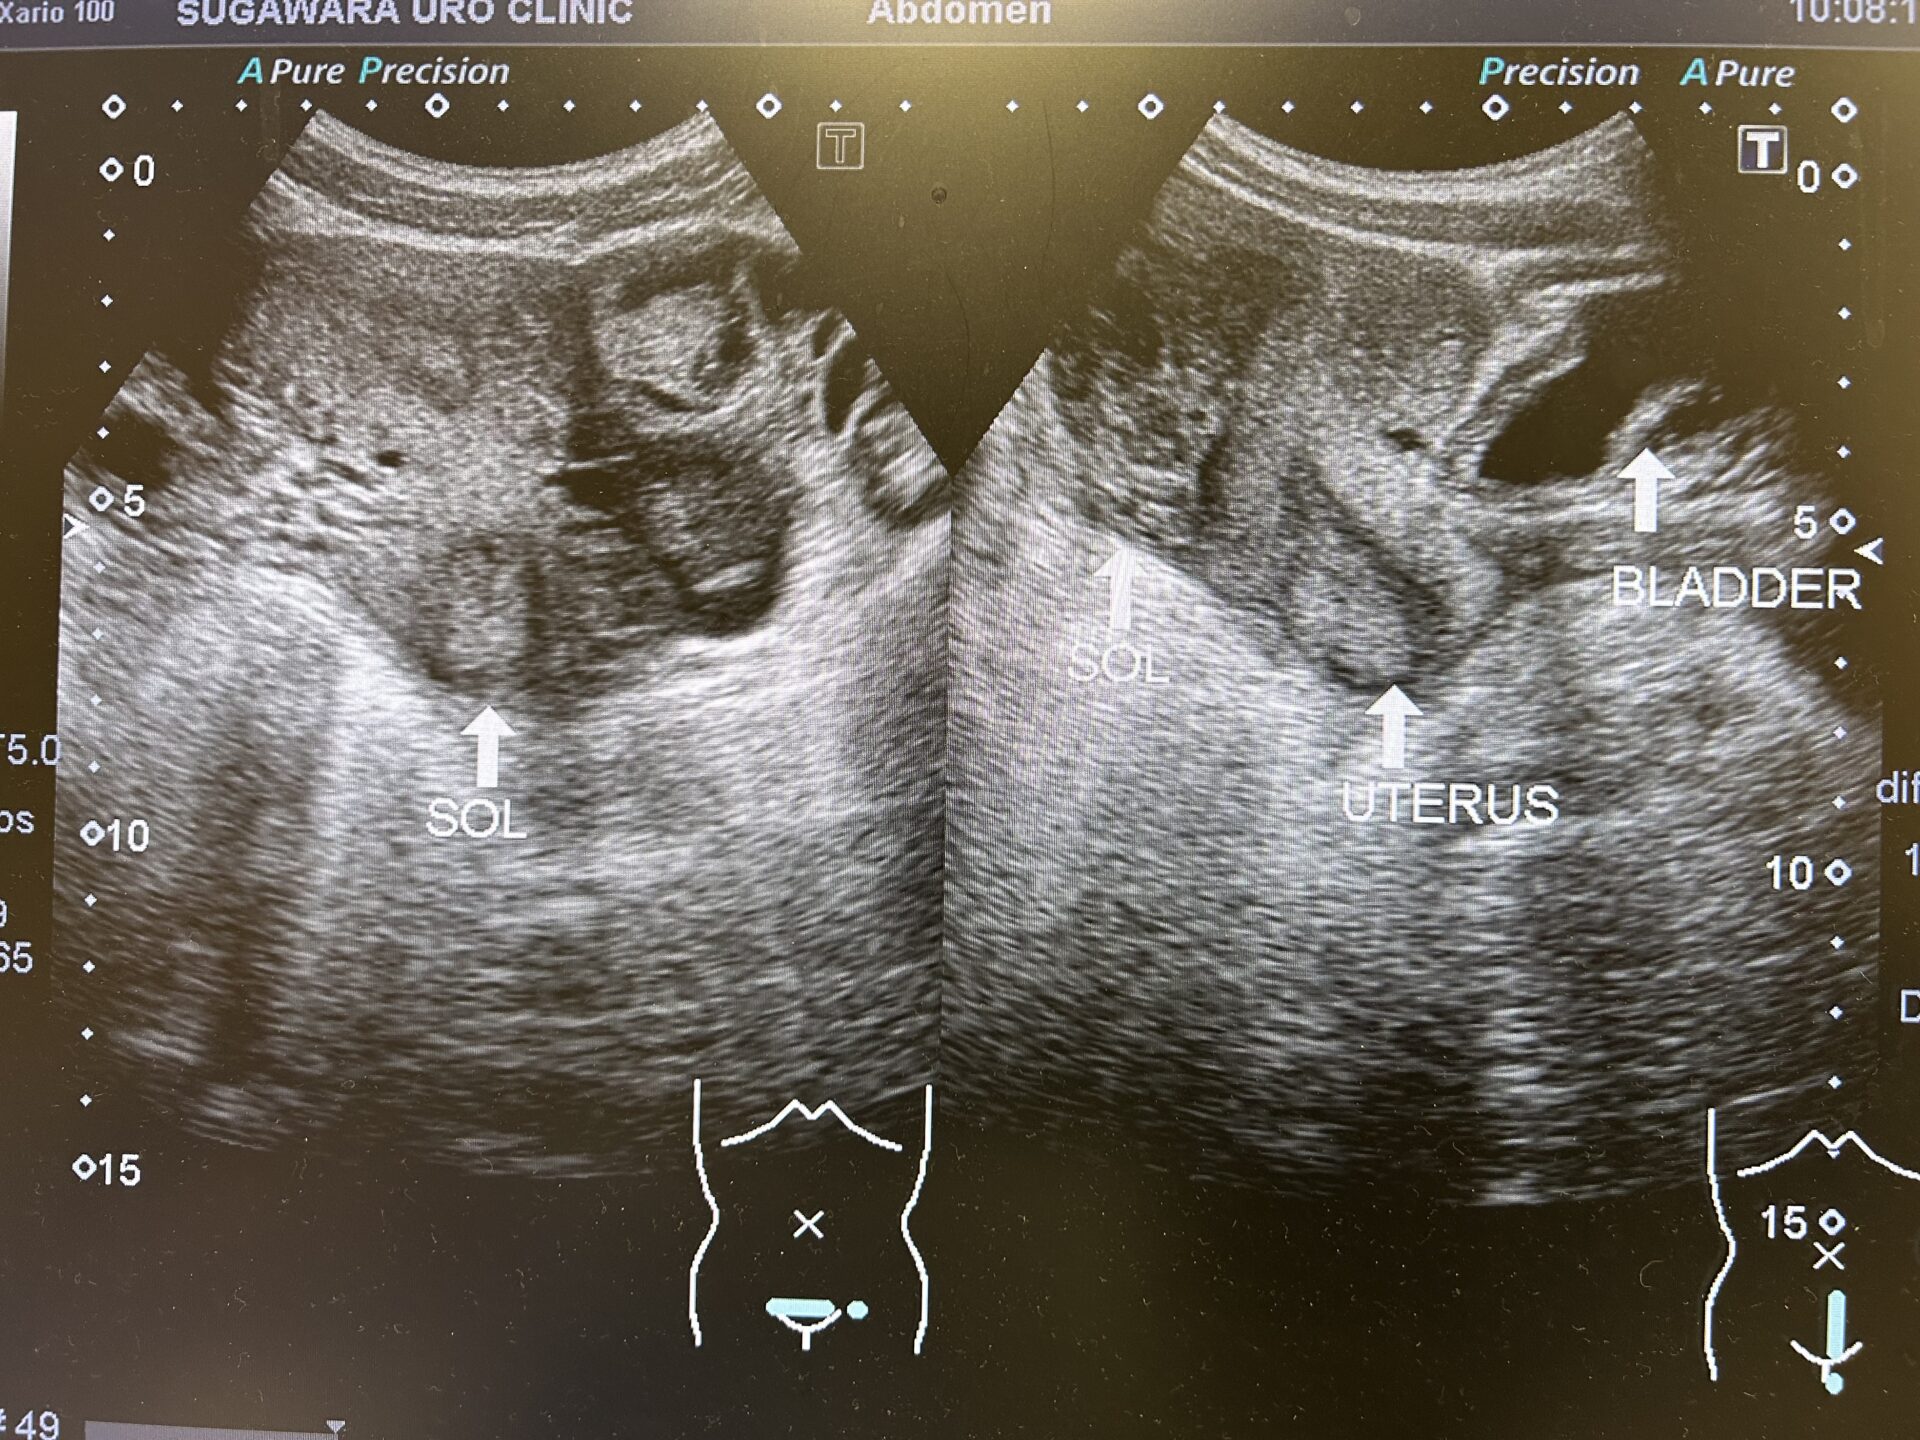

その後、尿路エコーを行ったところ、両側腎は異常なし。膀胱内も異常なし。しかし、矢状断で膀胱と子宮は異常無かったものの、腹腔内に腹水か何らかの液体貯留と考えられる所見を認めたため、すぐさま近隣の病院へCT撮影の依頼をしました。

【尿路エコー像:腹腔内に何らかの液体貯留が認められております。】